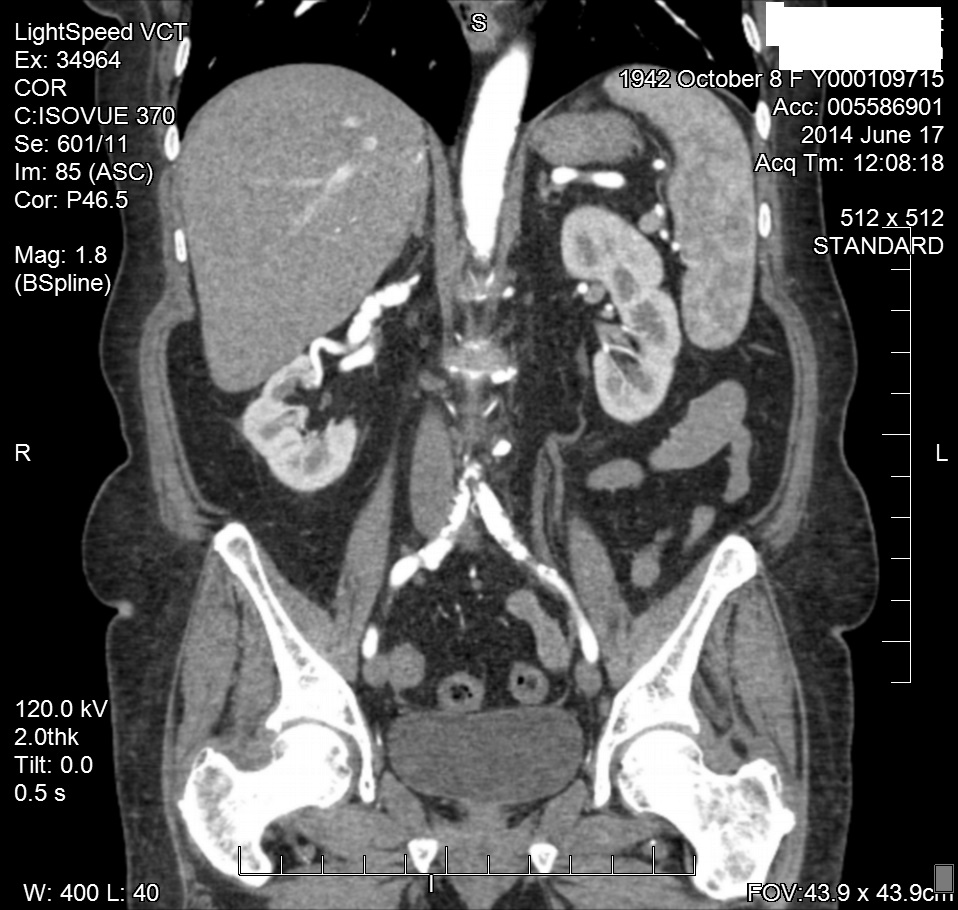

Upon obtaining the abnormal doppler findings, our interventional cardiologist performed an abdominal angiogram with selective bilateral renal arteriography. The angiogram demonstrated diffuse right renal artery haustra consistent with FMH. As well, abnormal retograde filling of the right renal vein and IVC was noted, and consistent with an AV fistula within the right renal artery helium (Figure 4). The left renal artery was normal on preliminary imaging, but remained suspect. Upon IVUS (Intra Vascular Ultra Sound) imaging, a significant (20mm) gradient was noted within the left distal renal artery.3 Bilateral cutting balloon angioplasties were performed and the patient was then sent to CPRU for recovery (Figure 5 & 6).

Figure 4 CTA of RRA FMD.

Two months later, the patient was referred to the radiology department for additional imaging with CTA. The CTA of the abdomen verified the “banded” appearance of both renal arteries consistent with FMH. The CTA also verified the angiographic findings of a right renal artery helium AV fistula or AV malformation. Since the bilateral renal artery angioplasties, the patient’s blood pressures have remained in the 130/70mm Hg range (Figure 7-9).